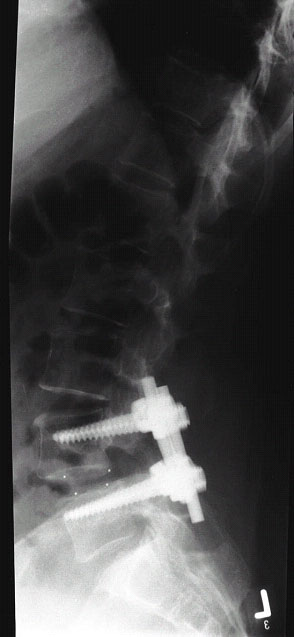

Abb.4-6

Seitliche Röntgenaufnahmen der selben Patientin nach der Operation (links) und nach einem Jahr (rechts). In jeden Wirbelkörper sind zwei Titanschrauben eingebracht (Bild mitte), verbunden sind die Schrauben mit jeweils zwei Titanstangen. Als Ersatz für die entfernte Bandscheibe dienen zwei Kunststoffwürfel (aus Carbon, erkennbar an punktförmigen Röntgenmarkierungen), welche mit dem Knochen des Patienten gefüllt sind. Auf dem rechten Bild ist die knöcherne Verbindung beider Wirbelkörper erkennbar.